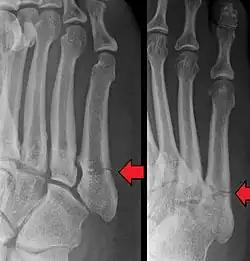

Jones fracture as seen on Xray

A Jones fracture is a broken bone in a specific part of the fifth metatarsal of the foot between the base and middle part .[8] In general, fifth metatarsal fractures heal readily, but a Jones fracture must be recognized and accurately diagnosed because of its higher rate of delayed healing or nonunion.[4] It results in pain near the midportion of the foot on the outside.[2] There may also be bruising and difficulty walking.[3] Onset is generally sudden.[4]

Diagnostic X-rays include anteroposterior, oblique, and lateral views and should be made with the foot in full flexion.

Other proximal fifth metatarsal fractures exist, although they are not as problematic as a Jones fracture. If the fracture enters the intermetatarsal joint, it is a Jones fracture. If, however, it enters the tarsometatarsal joint, then it is likely an avulsion fracture caused by pull from the fibularis brevis tendon. An avulsion fracture at the base of the fifth metatarsal is sometimes called a "dancer's fracture" or a "pseudo Jones fracture", and usually responds readily to non-operative treatment.[18] The X-ray appearance of the developmental "apophysis" in this area may have some resemblance of a fracture, but is not a fracture; it is the secondary ossification center of the metatarsal bone. It is a normal finding that occurs at this site in adolescents.[19] If an injury to that area has occurred, the physician is often able to interpret certain radiographic clues to make the differentiation. An avulsion fracture at this location is typically extra-articular and oriented transversally as compared to the longitudinal orientation of an unfused apophysis.[19]